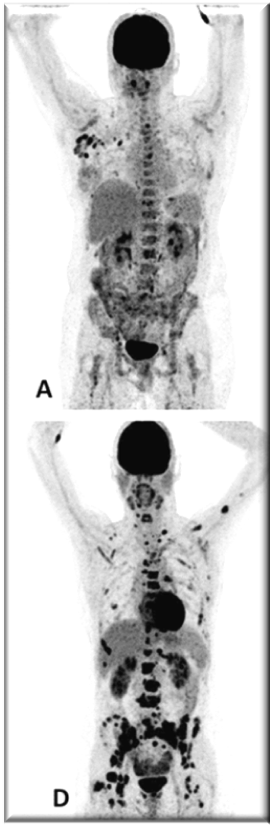

PET images of two patients with metastatic invasive lobular carcinoma responding (A-C) and not responding (D-F) to palbociclib + letrozole

Adapted with permission from Boers, J., et al. European Journal of Cancer. 2020; 126: 11-20

Upper row responder: (A) Baseline [18F]FDG-PET shows pathological uptake in axillary lymph nodes (right side) and in nearly all vertebrae and pelvic bones. (B) Baseline [18F]FES-PET with pathological ER expression in the axial skeleton (vertebrae, pelvic bones, proximal humeri and femora) and in axillar lymph nodes. (C) [18F]FDG-PET after 8 weeks shows almost complete metabolic response. The patient has been on treatment for more than 70 weeks.

Lower row non-responder: (D) Baseline [18F]FDG-PET shows pathological uptake in multiple skeletal lesions. (E) Baseline [18F]FES-PET with only some increased ER expression in thoracic vertebrae. (F) [18F]FDG-PET after 8 weeks shows no metabolic response, with some increase in the pathologic uptake in the multiple skeletal lesions.